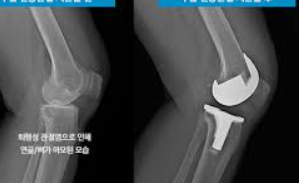

인공 관절 수술은 관절의 퇴행성 변화, 외상, 또는 다른 질환으로 인해 손상된 관절을 인공적인 재료로 만든 관절로 교체하는 의료 절차입니다. 이 수술은 주로 무릎, 고관절, 어깨 관절 등에 적용되며, 환자의 삶의 질을 향상시키고 통증을 감소시키는 데 목적이 있습니다.

인공 관절 수술의 종류는 크게 두 가지로 나뉩니다: 전치환술과 부분치환술입니다. 전치환술은 손상된 관절 전체를 인공 관절로 교체하는 방법이며, 부분치환술은 손상된 관절의 일부만을 교체하는 방법입니다. 환자의 상태와 필요에 따라 적절한 수술 방법이 선택됩니다.

반면, 부분치환술은 관절의 손상이 비교적 제한적인 경우에 적합합니다. 이 수술은 절개 부위가 작고 회복이 빠르며, 무릎 운동 범위의 제한이 적다는 장점이 있습니다. 특히, 연골 내측만 손상된 경우나 십자인대 기능이 정상인 경우에 시행됩니다.